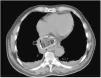

La miopericarditis es una enfermedad poco frecuente, predominando la etiología vírica, pero también puede deberse a una causa traumática directa o indirecta (por contigüidad). Presentamos a un varón de 76 años que acudió por dolor centrotorácico irradiado a escápula de 2 días de evolución, febrícula y disfagia a sólidos y líquidos. Se realizó electrocardiograma (fig. 1) donde se observa una elevación del segmento ST en las derivaciones precordiales. Analíticamente, PCR de 329.6mg/dl y elevación de troponinas de 1,695.8 pg/ml (normal 0-20). Ingresó por sospecha de miopericarditis aguda. Se realizó TC torácica (figs. 2 y 3) que informa de imagen cálcica localizada intraluminalmente en esófago de 55×50mm, que depende de pared esofágica derecha compatible con divertículo epifrénico con material luminal en su interior. Ante los hallazgos, el empeoramiento clínico y la ausencia de respuesta a antiinflamatorios, decidimos la realización de esofagogastroscopia (fig. 4 A y B), en la que se identifica dicho divertículo esofágico, con un hueso de ciruela, una pastilla y restos alimentarios en su interior, que se extraen secuencialmente con asa. Cabe destacar la presencia de lesiones por decúbito en la mucosa intradiverticular (fig. 5). Probablemente, la miopericarditis fuera producida por causa mecánica debido a la afectación del miopericardio por la inflamación transmural provocada por los cuerpos extraños retenidos en el divertículo (figs. 2 y 3). Tras la extracción, el paciente mejora y es dado de alta en 72 h.